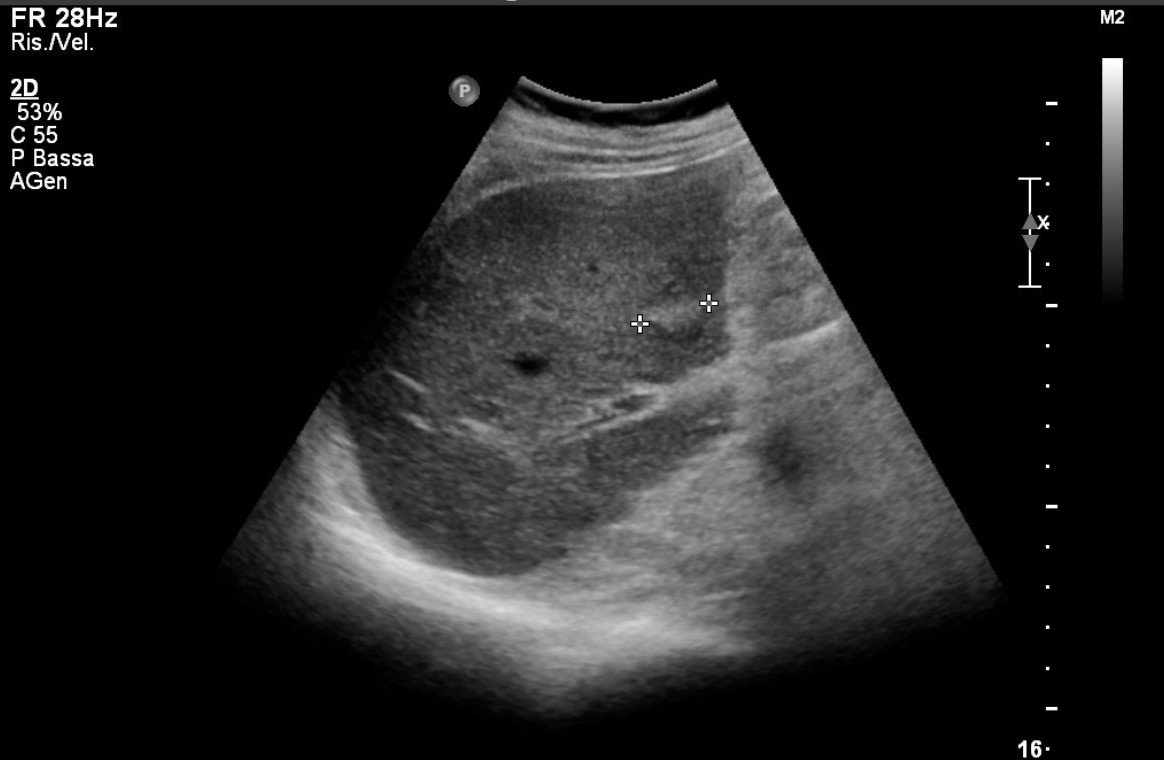

Ad oggi sono state identificate con l’ecografia addominale prevista dal protocollo, 9 neoplasie del parenchima epatico: 5 angiosarcomi (Fig. 1-4) (di cui 2 viventi) e 4 epatocarcinomi (Fig. 5-7) (di cui 1 vivente), successivamente sottoposte a studio TC e tutte confermate dalla diagnosi istologica.

Fig.2. Caso 1 di angiosarcoma epatico

Fig.3. Caso 2 di angiosarcoma epatico